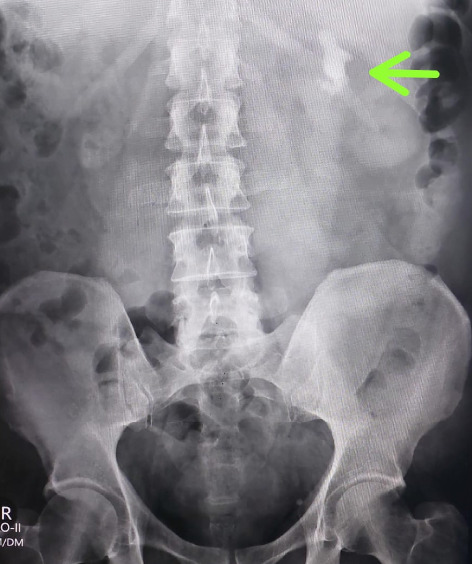

Background: After percutaneous nephrolithotomy (PCNL), intravenous misplacement of a nephrostomy tube is a very rare clinical occurrence. This report summarizes the characteristics and management of intravenous misplacement of a nephrostomy tube. Case Presentation: We present a rare case of intravenous nephrostomy catheter misplacement after PCNL in a 63 years old male. The tip of the tube was located in the left renal vein. The patient was managed conservatively and treated safely. Conclusion: Intravenous nephrostomy tube misplacement is a rare PCNL complication. Good Imaging can rule out through and through renal vein perforation and thus patients can be safely managed using conservative approach.

Abstract Image